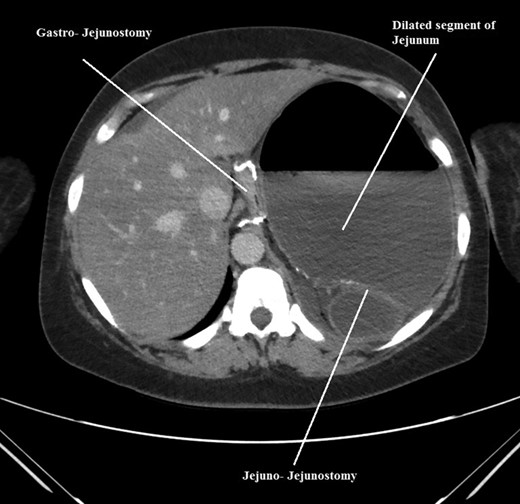

The intraoperative findings were not consistent with the radiological findings (Figs 1–4). As shown in the CT scan of abdomen and pelvis; multiple loops of dilated small bowel were seen, more predominantly dilated and matted bowel complex just above the spleen. The dilated bowel complex was decompressed using needle aspiration to help reduction of the bowel loops. The ileo cecal junction was then identified and traced back to the perisplenic hilar region. The trifurcation of three bowel loops (Roux limb, biliopancreatic limb and common limb) were identified with identification of ligament of Treitz. The prior gastric bypass was of ante colic- ante gastric type and Peterson’s defect was not closed. The above described bowel trifurcation had sunken postero- inferior to the spleen and had herniated through a potential space underneath the spleen and torsed around the splenic vessels and hilum. This picture was consistent with perisplenic small bowel volvulus. As noted earlier there was a massively dilated proximal small bowel segment above the spleen, displacing it caudally. Careful adhesiolysis was performed inferior to the spleen to release the segment of the trifurcation. The bowel segments once reduced were assessed and appeared viable. Of note, the spleen appeared better perfused after reduction. The remnant hernia defect of size 2 × 3 × 2.5 cm around the hilar region was then approximated using interrupted non-absorbable sutures. Enterotomy at the decompression site was closed with non absorbable suture. All potential sites of IH were re-examined and there was no evidence of any other internal herniation. Coelomic cavity was thoroughly irrigated and operation concluded successfully. Postoperative hospital stay was uneventful, and the patient was discharged home after two days.

Coronal CT scan of abdomen and pelvis showing Volvulized segment of bilio-pancreatic limb and its mesentery in the spleen hilum.